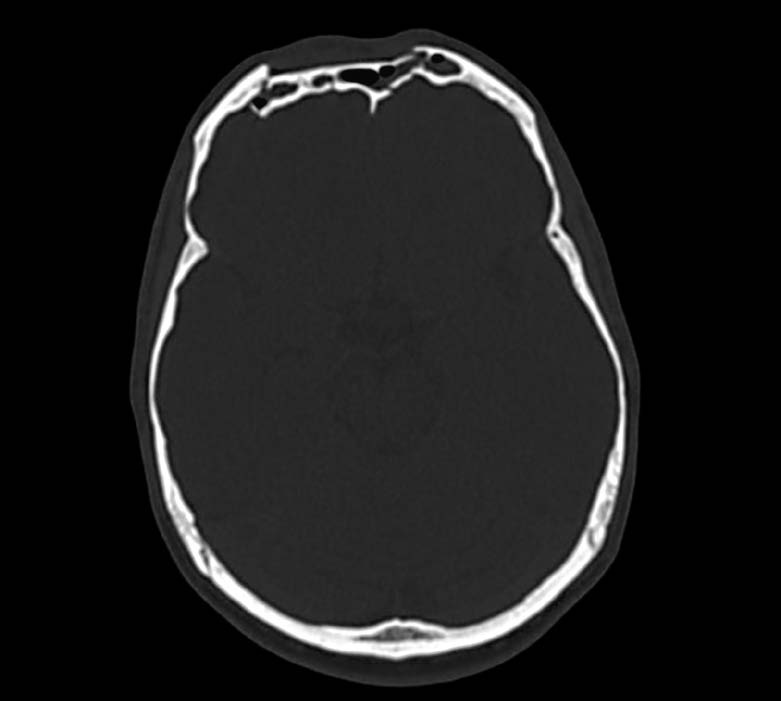

На снимке по МСКТ головного мозга в аксиальной проекции определяется депрессионный вдавленный многооскольчатый перелом теменной кости слева.

На снимке по МСКТ головного мозга в аксиальной проекции определяется депрессионный вдавленный многооскольчатый перелом теменной кости